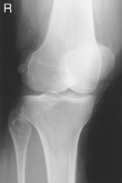

• Supine, or seated on table, with leg extended and centered to CR and midline of table or IR

• Rotate leg slightly inward as needed to place knee and leg into a true AP. Center IR to CR.

Medial oblique: Demonstrates fibular head and neck unobscured. (Lateral oblique may also be taken.)

• Prone, knee centered to CR and midline of table or IR

• If patella area is painful, place pad under thigh and leg to prevent direct pressure on patella.

• Rotate anterior knee approximately 5° internally or as needed to place an imaginary line between the epicondyles parallel to the plane of the IR.